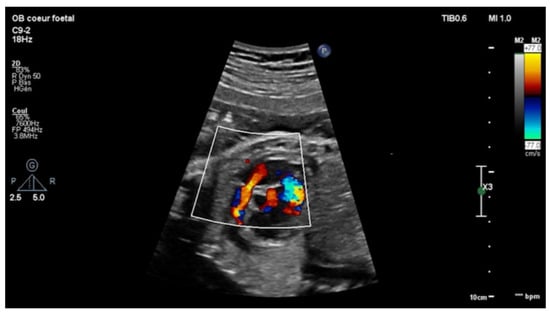

Echocardiography in a fetus at 25 weeks of gestation (WG) from a 19-year-old woman, without history of familial CHD, showed: (i) a typical partial common AVCD with a cleft on the left atrioventricular valve (AVV) without stenosis or leak and a large ostium primum atrial septal defect (ASD); (ii) Ebstein abnormality of the right AVV with a significant leak, causing a dilatation of the right atrium (RA) (Figure 1; Videos S1 and S2); (iii) “functional pulmonary atresia” with inconstant anterograde passage and (iv) retrograde flow in a tortuous ductus arteriosus. Other cardiac structures were normal. Cytogenetic analysis via amniocentesis had normal results. At 30 WG, moderate atrialization of the right ventricle and a pulmonary insufficiency were noted (Figure 2).

Figure 2. Short-axis view: color Doppler: retrograde flow in the pulmonary artery with pulmonary insufficiency.